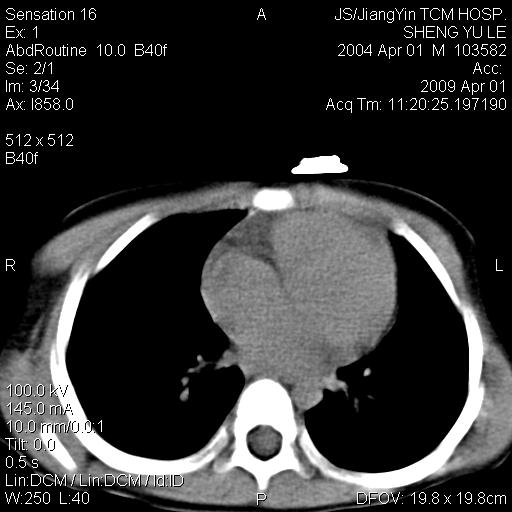

m,5岁。尿痛尿频数天。既往无病史。ct平扫腹盆腔积液。膀胱壁明显增厚。另可见心包增厚。wbc5万,骨髓穿等结果。请指教。

膀胱影像表现结合临床应该是急性膀胱炎症,但为什么有腹水呢?双肾输尿管无扩张,泌尿系压力应该不大不至于引起尿外渗,应该是腹膜感染引起的,但楼主没有提及相关症状,腹膜及膀胱结核?患者白细胞5万(结核不至于这么高啊),脾脏增大,是不是有白血病?进一步检查。。